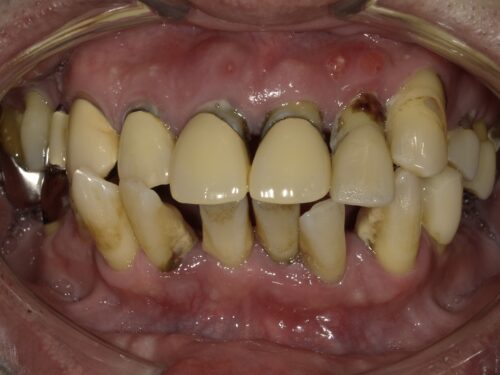

歯周病で歯がグラグラしてしまって来院された患者さんです。

長年お悩みだったようです。

グラグラしてる影響か、前歯が傾いてきてしまっています。

歯ぐきの周りに歯石がついているのが見えます。

歯ぐきも赤く腫れ上がっていますが、

歯周病はそこまで痛みがないので

気づかないうちにここまで進んでしまっていた、なんてこともよくあります。

自覚症状は強くないですが、

重度歯周病の歯はほうっておくとどんどん周りの骨を溶かしていってしまうので、

抜歯をすることで骨の炎症を治さなければなりません。

奥歯も残っていますが歯周病で根元まで見えてしまっていたり、

歯の向きが変わってしまっているところもあります。

下の大臼歯とよばれる奥歯はもうありませんでした。